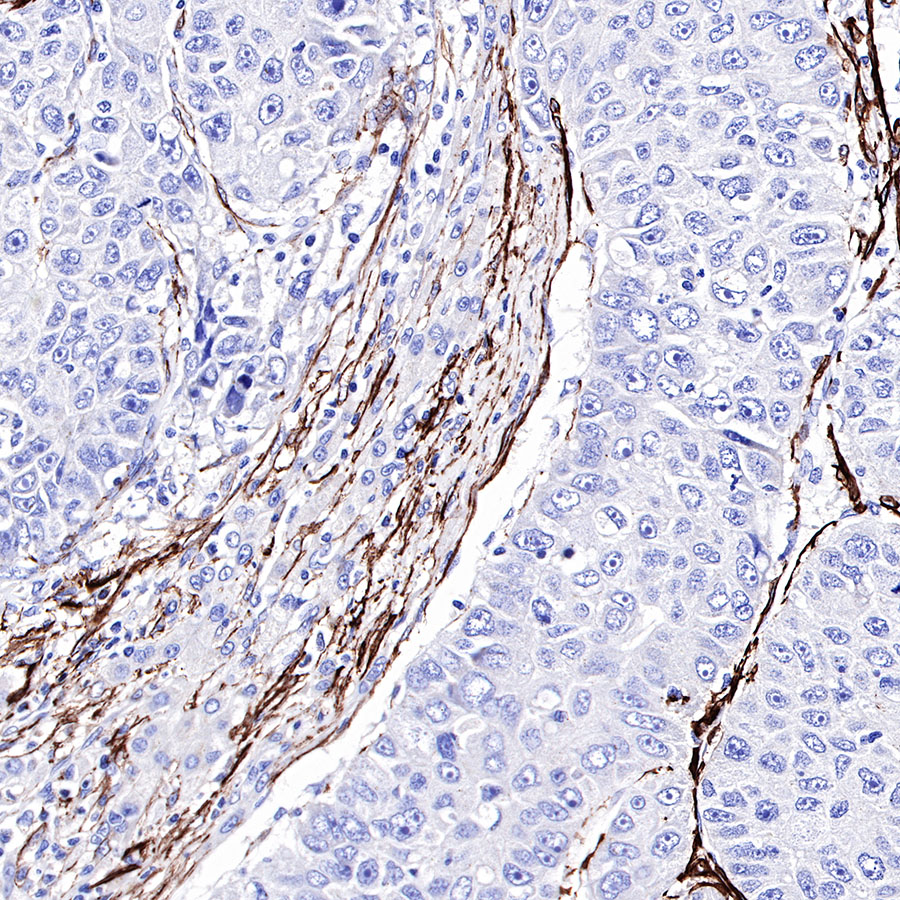

Immunohistochemistry